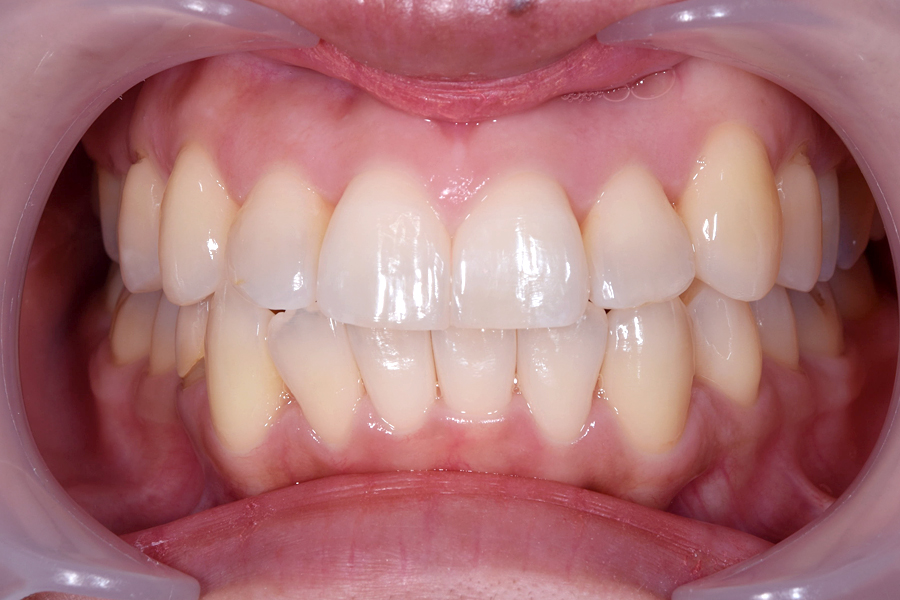

| 主訴 | 見た目を治したい、歯を白くしたい |

| 治療期間 | 1年6か月 |

| 治療費 | マウスピース矯正と ホームホワイトニングセット 1,022,350円(税込) |

| 治療内容 | 目立ちにくいマウスピース矯正 (非抜歯矯正) 歯と歯の間に隙間をつくることにより、歯列弓を広げながら治療を行いました。 また矯正用マウスピースをトレー代わりにし、ジェルを入れてホームホワイトニングを同時に行っております。 |

| 治療のリスク | ・後戻りする可能性があるのでリテーナーを最低でも矯正期間以上はつける必要があります。 ・ホワイトニング後、一時的に痛みが出る場合があります。 |